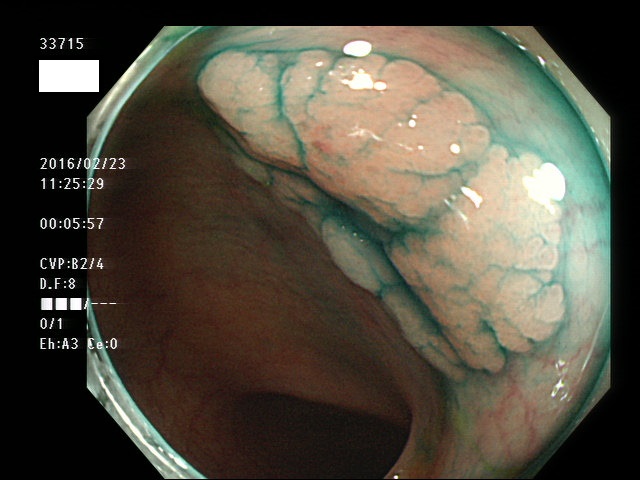

上記100名より抽出した平坦・陥凹型腺腫(=癌化の危険が高いが見落としやすい病変)の内視鏡写真